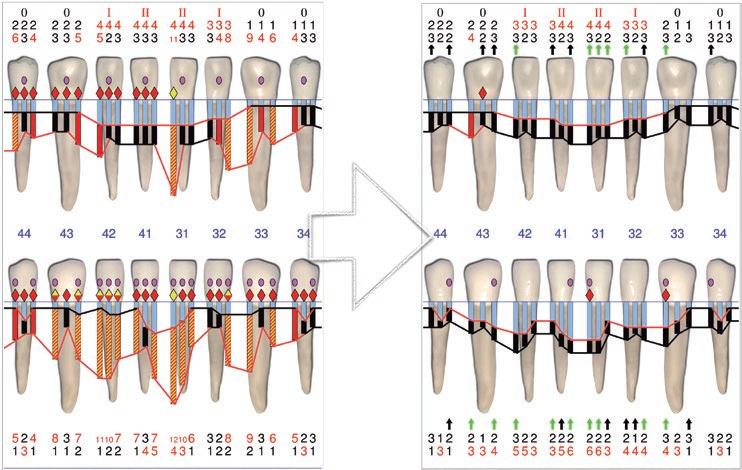

Esta es una pregunta con difícil respuesta. Realmente el límite lo ponen los factores anteriormente nombrados. Cada uno de ellos debería analizarse en conjunto para decidir si un caso es o no susceptible de regeneración. Si nos centramos específicamente en los factores del defecto (número de paredes, ángulo del defecto, profundidad del defecto, movilidad dental, lesión endo-periodontal), ninguno de ellos per se puede ser suficiente como para justificar la imposibilidad de realizar una regeneración periodontal con el objetivo de mantener el diente en boca. Ni siquiera la inserción dental remanente, por mínima que sea, incluso llegando a ser nula. El caso que presento (caso 3) es un ejemplo de ello. Mujer de 68 años, exfumadora hace 20 años de 10 cigarrillos/día, sin patologías sistémicas. Acude a nuestra clínica con el siguiente motivo de consulta: “Tengo mucho miedo de perder mis dientes. Llevo muchos años con movilidad y me gustaría que hicieran lo posible por evitar extracciones”. La paciente presentaba una periodontitis estadio III, grado A10; con vitalidad negativa en el diente 31 (fig. 3.1). Tras su diagnóstico completo, decidimos hacer un tratamiento periodontal básico e instrucciones de higiene oral (fig. 3.2). Posteriormente derivamos el caso a nuestro endodoncista, el doctor Luis Costa, quien comenzó el tratamiento endodóntico del diente 31 colocando hidróxido de calcio y ferulizando el diente 31 al 32. Una semana después finalizó la endodoncia del mismo con su correspondiente obturación y sellado coronal. Tras un periodo de cuatro meses, la paciente seguía presentando sondajes periodontales muy profundos en todo el 5º sextante. La radiografía periapical del 31 a los cuatro meses mostraba la ausencia de regeneración del defecto con el tratamiento realizado hasta la fecha. Incluso se podía apreciar un posible desplazamiento del ápice del diente 31 (fig. 3.3). Dada la situación clínica, decidimos hacer un tratamiento regenerativo de todo el sextante mediante una técnica quirúrgica de preservación de papila modificada36 aplicando únicamente proteínas derivadas de la matriz del esmalte (fig. 3.4). El problema surgió cuando la ferulización del 31 se rompió durante el raspado y alisado radicular del diente (fig. 3.5). Dado que el tratamiento regenerativo estaba destinado a todo el sextante y no solo al 31 (fig. 3.6), decidimos seguir adelante con nuestra intervención con la intención de mantener “todos” sus dientes. Colocamos el diente avulsionado en suero fisiológi-

co y continuamos con el desbridamiento de todo el área a tratar. Al finalizar el raspado y alisado radicular, eliminamos los dos últimos milímetros del ápice del incisivo avulsionado (fig. 3.7) y lo volvimos a reponer en su sitio ferulizándolo en una posición ligeramente más apical a la original, con la intención de aproximar la raíz al defecto y facilitando la ausencia de oclusión del susodicho diente (fig. 3.8). A continuación, aplicamos EDTA al 24 % durante 2 minutos, lavamos, secamos y aplicamos proteínas derivadas de

la matriz del esmalte sobre las superficies radiculares de los dientes a tratar (fig. 3.9). Finalmente, suturamos consiguiendo un cierre por primera intención. Retiramos la sutura a las dos semanas y pasamos a la paciente a fase de mantenimiento periodontal. Como en todos los casos de regeneración periodontal que tratamos, realizamos un mantenimiento periodontal de la zona regenerada al mes, 2 meses, 3 meses, 6 meses, 9 meses y 12 meses. En la cita de los 6 y 12 meses aprovechamos para hacer un man-

tenimiento periodontal de toda la boca. Así, al cumplir un año desde la regeneración, realizamos una reevaluación periodontal y radiografía periapical (figs. 3.10 y 3.11). Como se puede apreciar en el periodontograma y radiografía periapical, el objetivo de mantener sus dientes en boca se había conseguido. Lo más interesante es ver cómo, con el paso de los años, el hueso alveolar siguió aumentando alrededor de los dientes tratados (fig. 3.12), así como su inserción periodontal. A partir del año se realizaron mantenimientos periodontales cada seis meses hasta el día de hoy (fig. 3.13), llevando todos sus dientes en boca más de cinco años desde la regeneración periodontal (fig. 3.14). Este tipo de resultados no es un hecho aislado. Cortellini y colaboradores publicaron en 201137 un artículo en el que trataron 25 pacientes con defectos periodontales más allá del ápice con